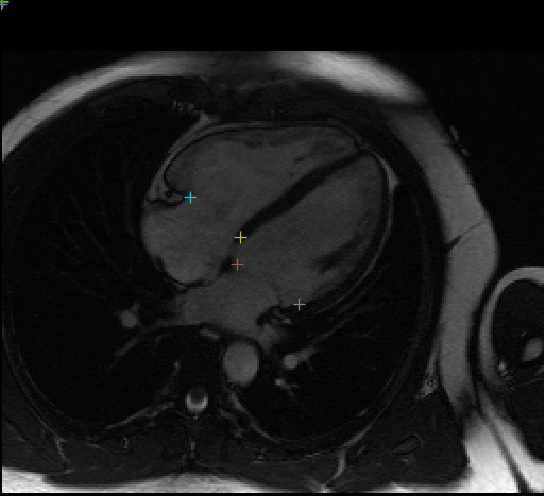

Example plot of landmarks on a single frame, see view_results.ipynb for visualising network output:

This network identifies 10 different landmarks in 2D+t MR images of the heart (2 chamber, 3 chamber, and 4 chamber) representing the insertion locations of valve leaflets into the myocardial wall. These coordinates are used in part of the construction of 3D FEM cardiac models suitable for physics simulation of heart functions.

Input images are individual 2D slices from the time series, and the output from the network is a (2, 10) set of 2D points in HW image coordinate space. The 10 coordinates correspond to the attachment point for these valves:

- Mitral anterior in 2CH

- Mitral posterior in 2CH

- Mitral septal in 3CH

- Mitral free wall in 3CH

- Mitral septal in 4CH

- Mitral free wall in 4CH

- Aortic septal

- Aortic free wall

- Tricuspid septal

- Tricuspid free wall

Landmarks which do not appear in a particular image are predicted to be (0, 0) or close to this location. The mitral valve is expected to appear in all three views. Landmarks are not provided for the pulmonary valve.